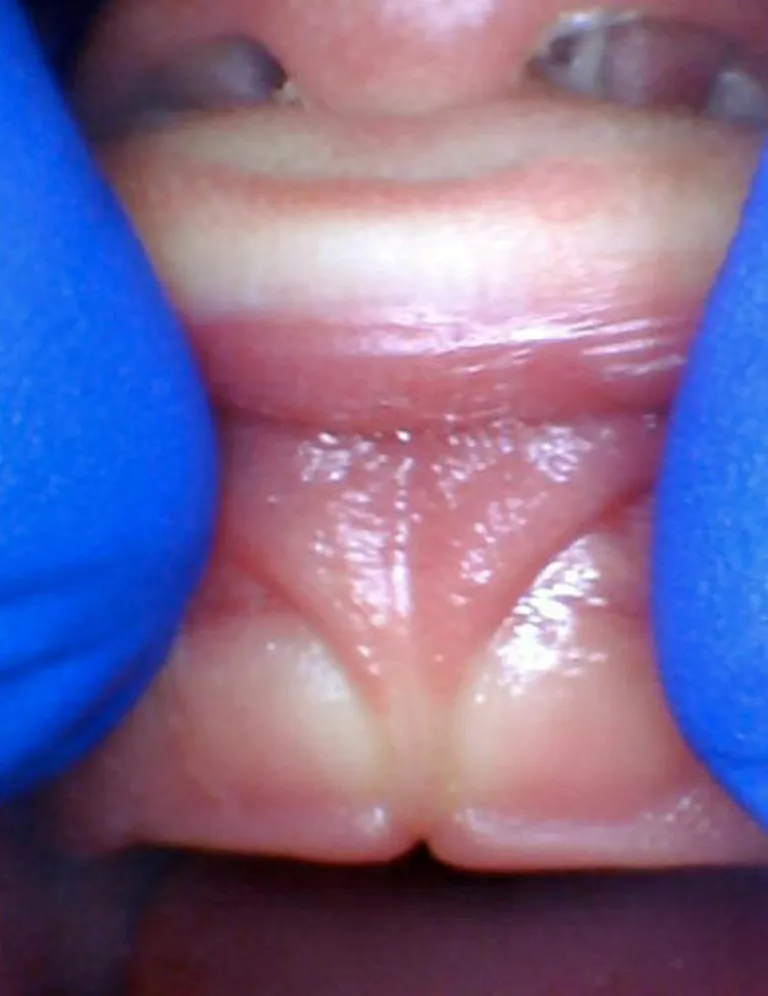

Photos ci-dessous issues du site Tongue-Tie Alabama avec l'accord de R. Baxter.

Bébé - Spectre de restrictions d'un FR lingual

Enfant - Spectre de restrictions d'un FR lingual